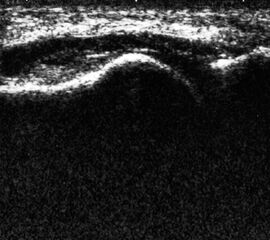

Referenzstruktur: Direkt unter der Haut und der dünnen Subkutis liegt echogen und straff parallel die Achillessehne mit ihrem echogenen Peritendineum (Abb. 53), Tuber calcanei.

Befunde: Da die Sehne zumeist nicht glatt, sondern bündelförmig reißt, stellen sich auch in der Sonographie anders als bei den Peroneal- und Flexorensehnen keine spargelspitzenähnlichen Rissenden dar. Echogene Rissränder, umgeben von echoarmem Hämatom sind beweisend für eine Ruptur. Risse der Achillessehne können auch nur einen Teil des Sehnenquerschnitts betreffen. Daher ist die Untersuchung verschiedener TS bedeutsam (Abb. 54 bis 56). Unter Kontrolle am Monitor kann die Diagnose in maximaler Dorsalextension klarer gestellt werden (Abb. 57).